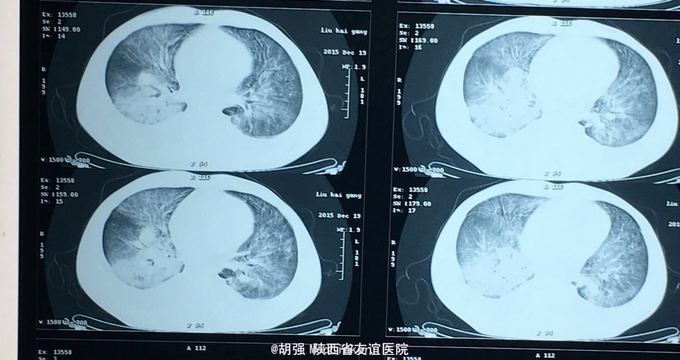

查体:口唇无发绀,咽充血,双侧扁桃体2度大,表面可见脓胎。两肺呼吸音粗糙,可闻及管状呼吸音。余查体无明显异常。 辅助检查:血常规提示白细胞及血小板明显低于正常值,肝功提示转氨酶升高。凝血系列:PT、APTT时间明显延长。T sport试验弱阳性。10月份胸部CT平扫未见明显异常。10月26日及12月12日胸片未见明显异常。12月19日胸部CT提示:两肺斑片状阴影,两侧胸腔积液。